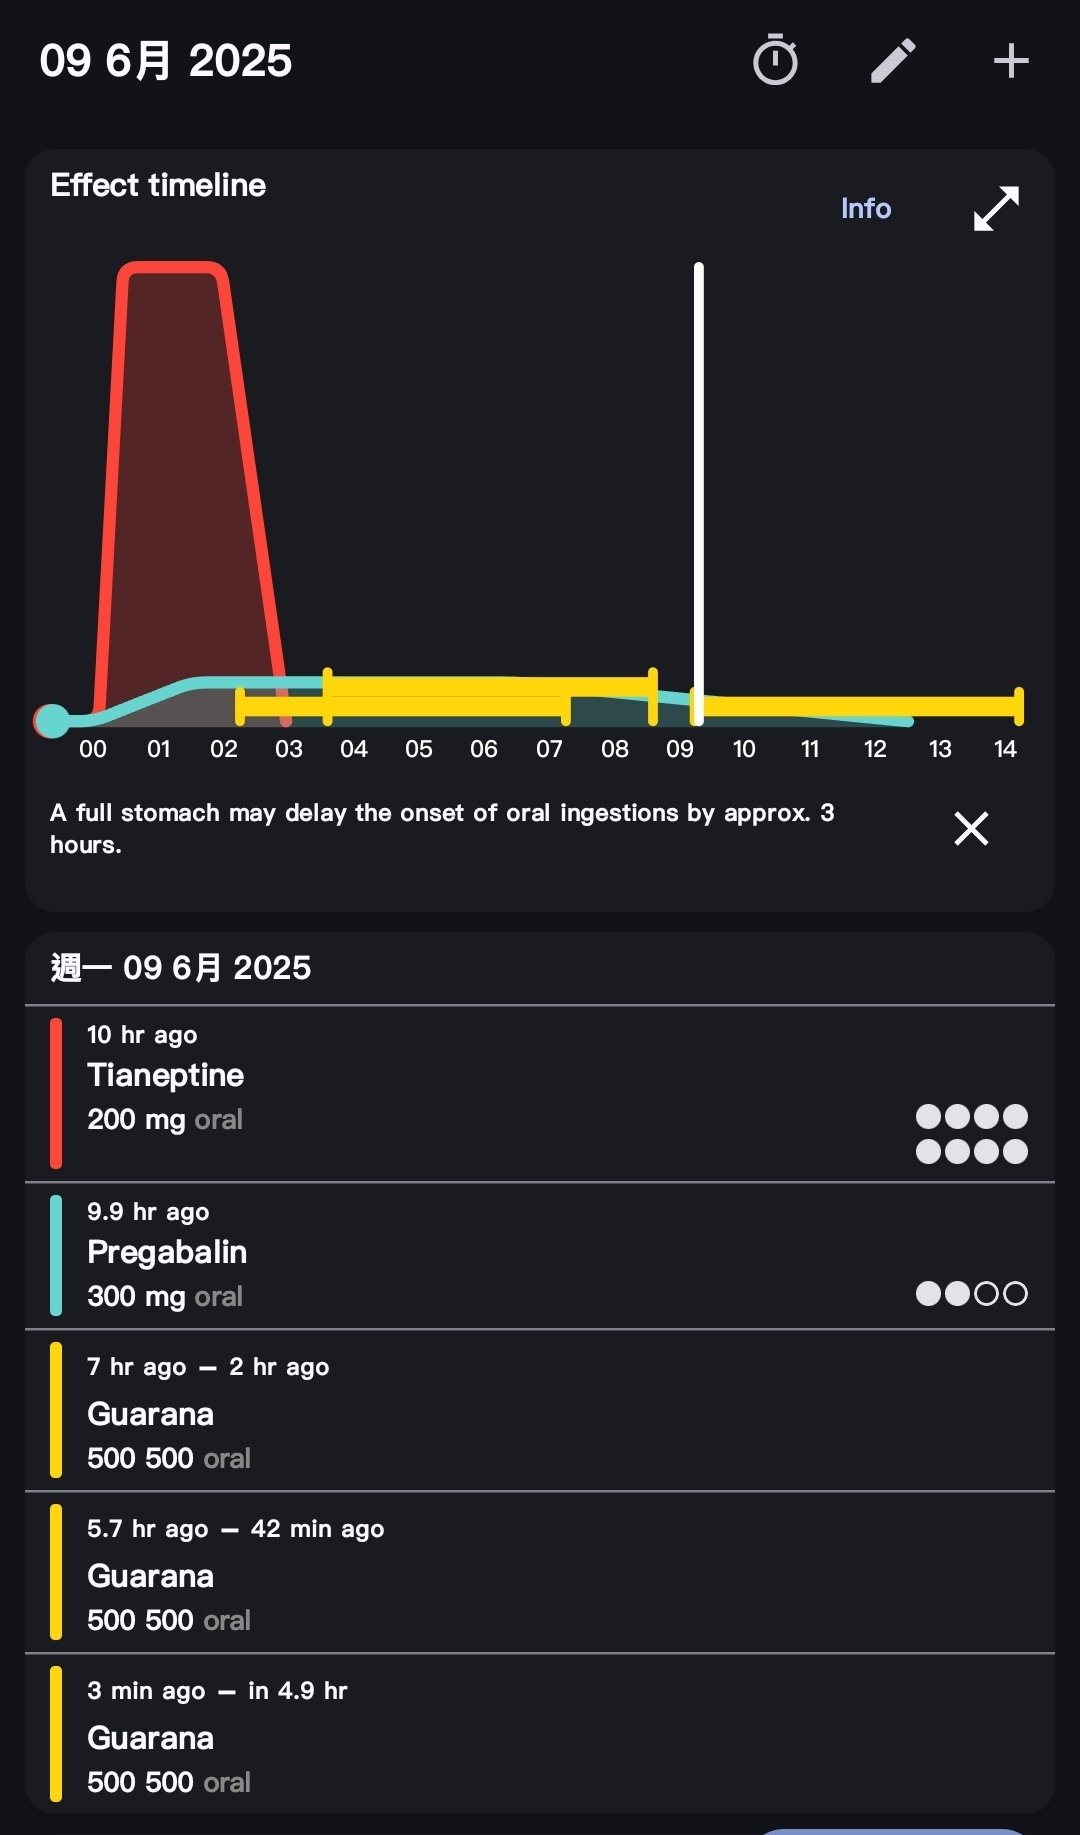

🥛💤 @Kumamushi2021@AnIncandescence 如果减少氨酚羟考酮的剂量,增加普瑞巴林和酒精的剂量呢……不过那样我可能会呕吐吧。有时候真恨自己不懂药理,连结束生命都要靠赌。

炽烈已极 @AnIncandescence@Kumamushi2021 如果真的到了非做不可的地步……或许我能提供帮助,这非常左右脑互搏!因为我也无法眼睁睁看着朋友选择痛苦的方式🥺…